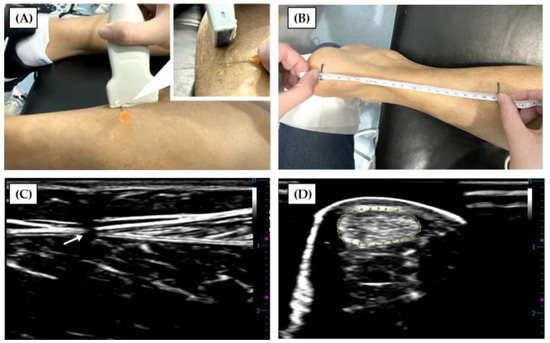

2. Materials and Methods